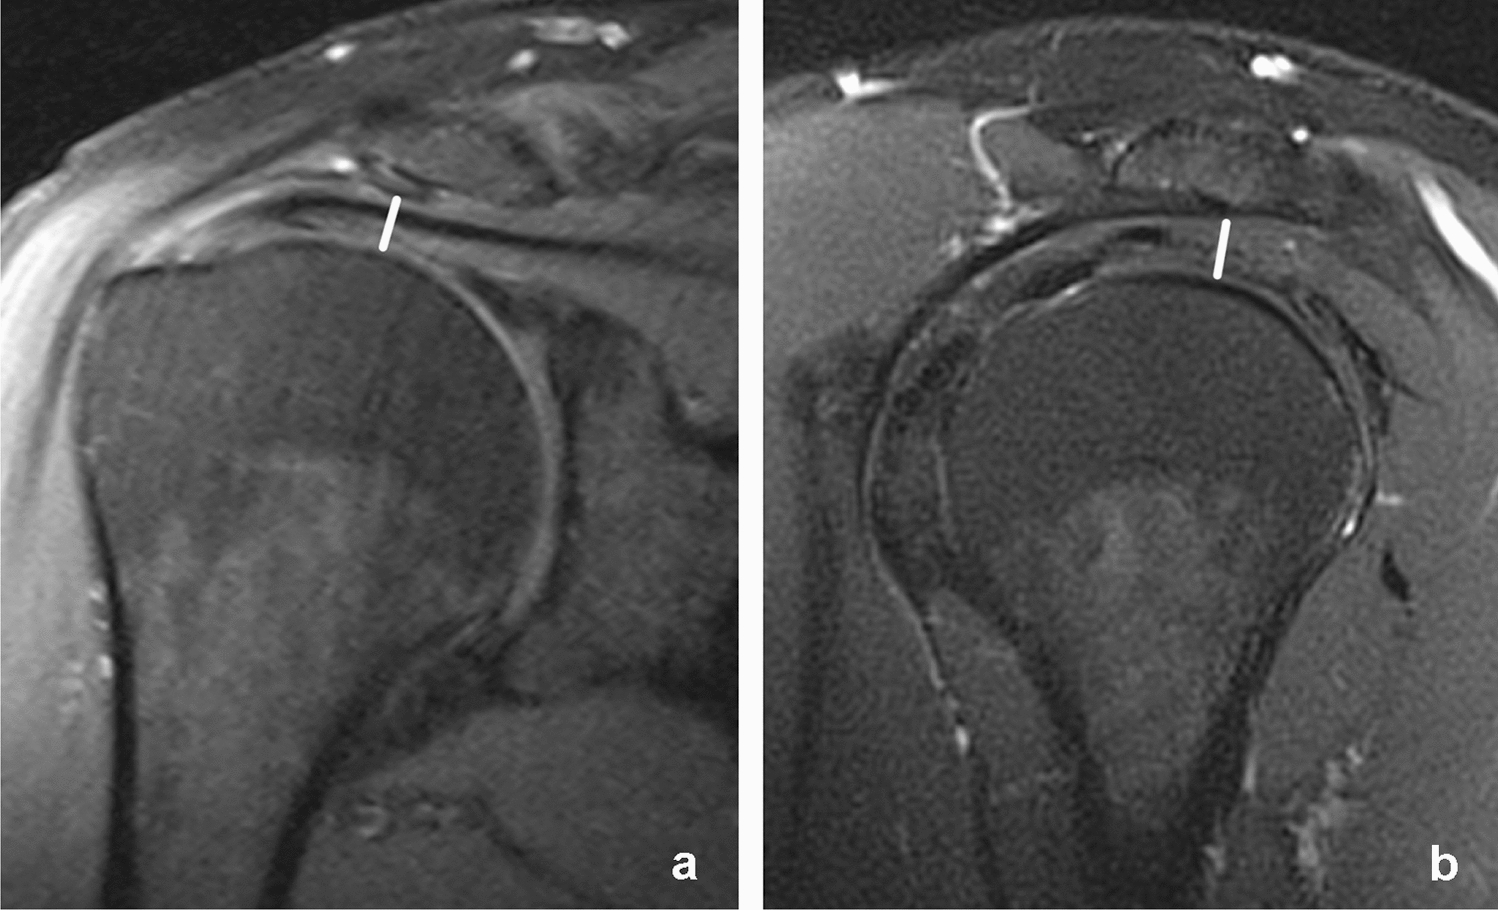

The measurement of the critical shoulder angle (CSA) was adapted to MRI as previously described by Spiegl et al. [20]. As the most lateral point of the acromion is usually located posteriorly to the glenoid the most lateral extent of the acromion in a coronal plane is marked with the cursor (see Fig. 2). After scrolling back to a plane that shows the glenoid and more central parts of the acromion, the critical shoulder angle was measured [20].

Fig. 2

Measurement of the critical shoulder angle. T1-weighted images in a coronal plane a, b. Transversal proton-density weighted fat saturated images c. The most lateral extent of the acromion is marked in a coronal plane (arrow in a). After scrolling to a coronal plane, representing the middle of the glenoid b, the critical shoulder angle was measured. The white line in c represents the imaging plane of b

Although involving scrolling through different imaging planes (see Fig. 2), adaption of the critical shoulder angle from conventional radiographs to MRI is a reliable measurement with almost perfect interrater variability (κ = 0.829; p < 0.001). This is remarkable since other authors only reported an inter-observer agreement of 0.62 for their method of measuring the critical shoulder angle [20]. One reason for this might be that other study populations consisted to one third of patients with osteoarthritis of the glenohumeral joint making it hard to identify the cranial and caudal border of the glenoid, which is needed for measuring the critical shoulder angle [20]. So the accuracy of measuring CSA in Impingement/rotator cuff populations seems to be more valid than in case of other pathologies.